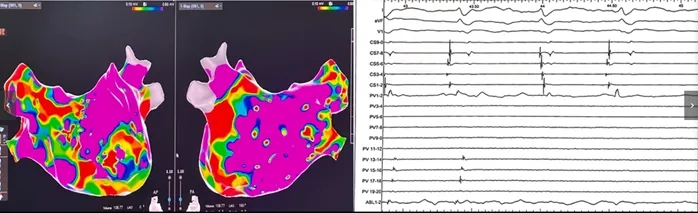

术中,心内电生理图显示冠状窦激动顺序及周长存在变化(图2)。左房电压标测提示前壁存在低电压区。双肺静脉区域可见瘢痕及延迟肺静脉电位(图3),提示既往曾尝试行环肺静脉电隔离术。鉴于房颤复发史,遂行补充消融以实现完全肺静脉隔离。

图2 心内电图显示冠状窦激动顺序变化

图3 左心房电压图及肺静脉电位

图注:(左图)左房电压图示前壁低电压区;(右图)双肺静脉可见瘢痕及延迟肺静脉电位